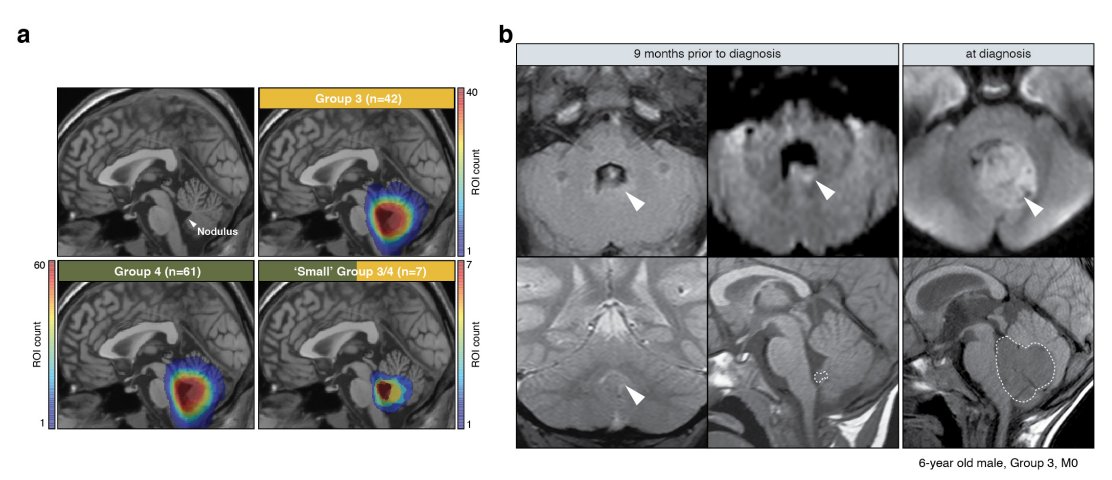

'Unified rhombic lip origins of group 3 and group 4 medulloblastoma': https://t.co/h5XeCAKJCc Matter of great honor to have coauthored this groundbreaking study @Nature with the honorable Zoltan Patay. Special thanks to @drpaulnorthcott and @parthivhaldipur! Some heat maps here: